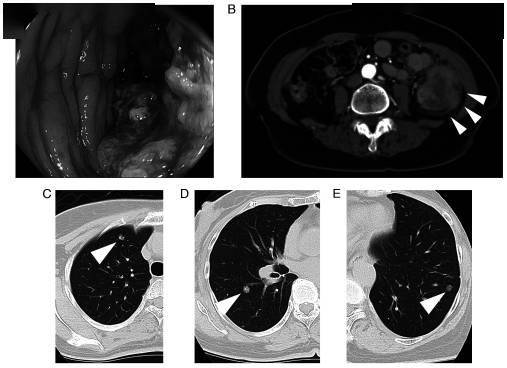

直肠癌一例

肿瘤病灶术前ct:箭头所指为左侧盆腔侧方淋巴结患者为局部晚期直肠癌

及局部放疗,治疗后盆腔ct如下,最终完成腹腔镜直肠癌根治术(保肛低位